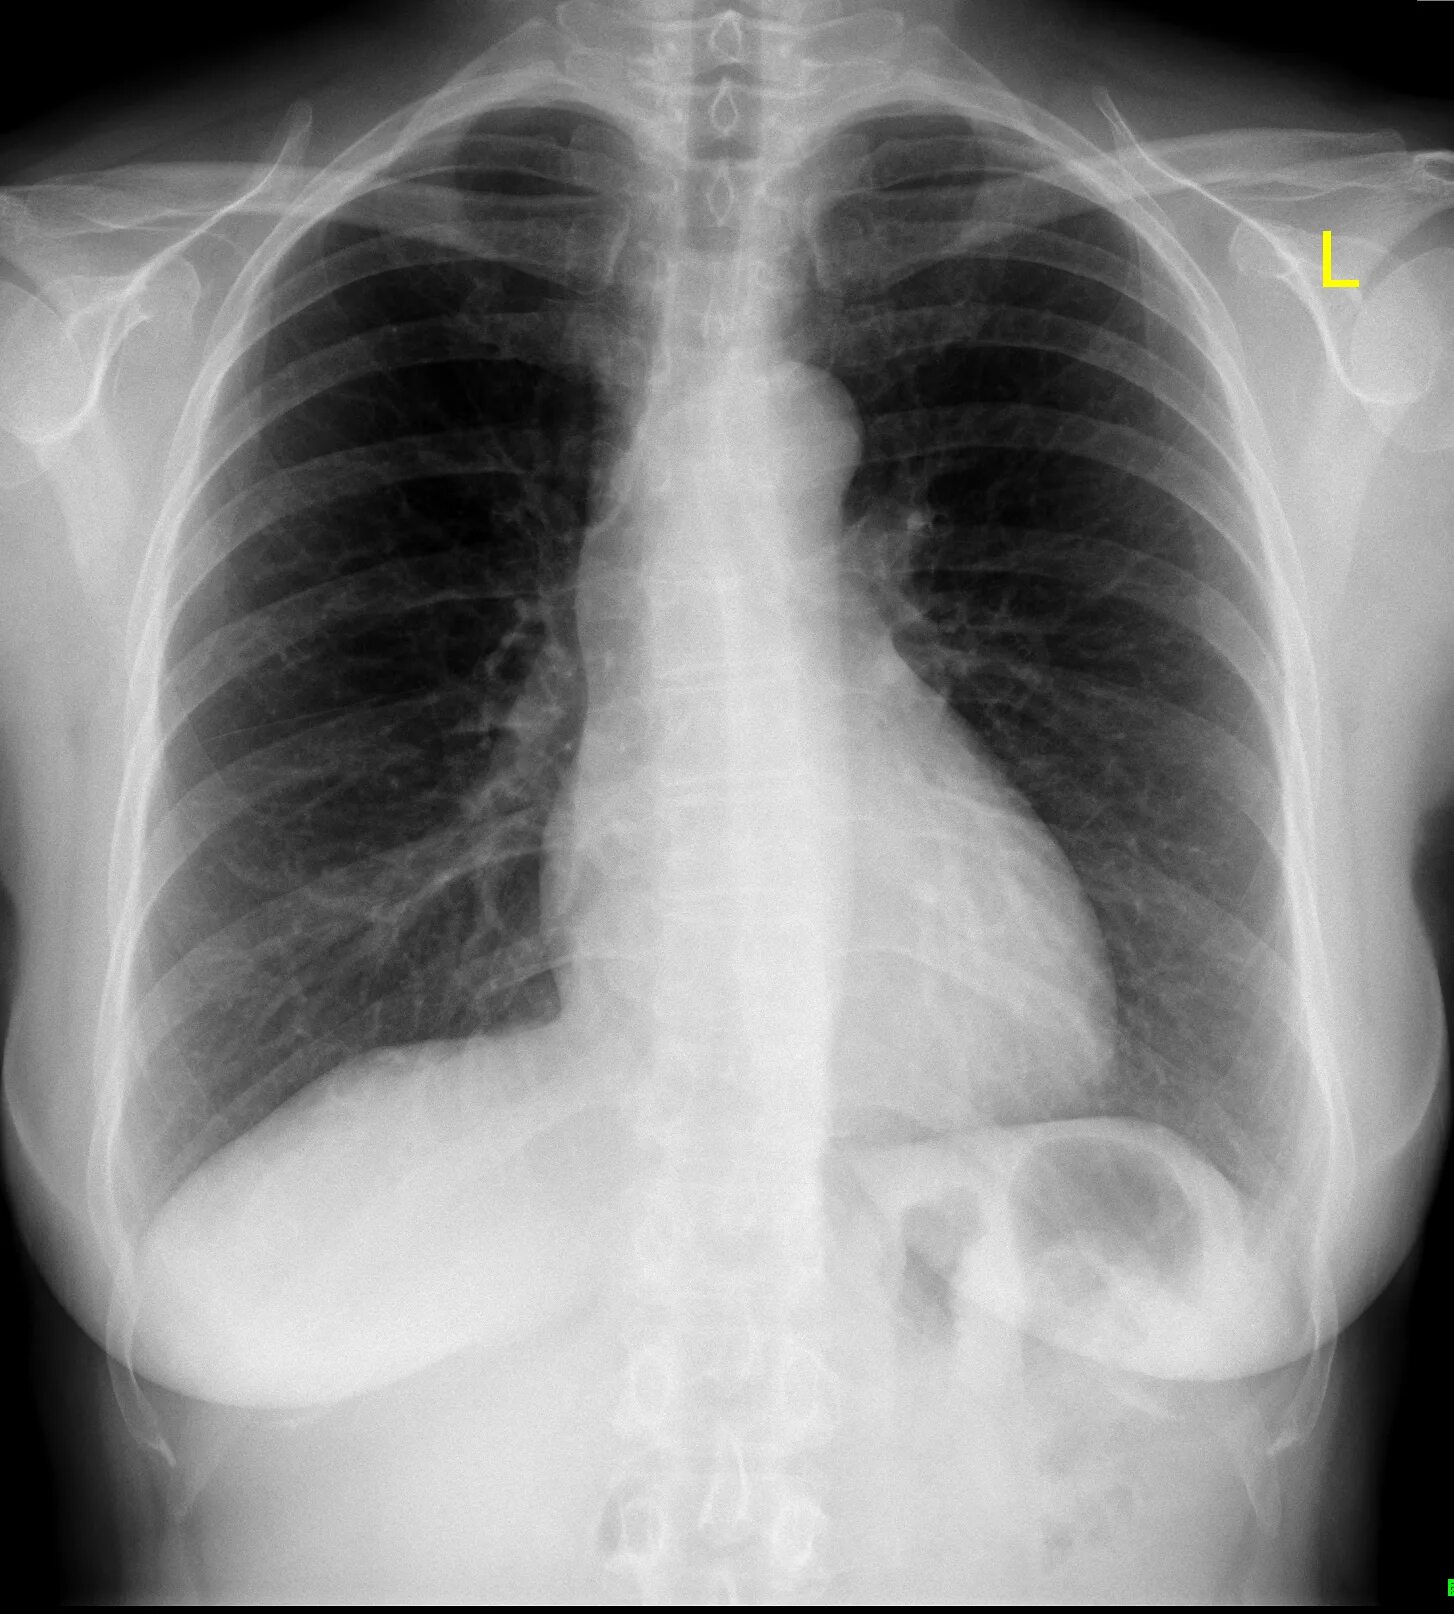

Source x rays